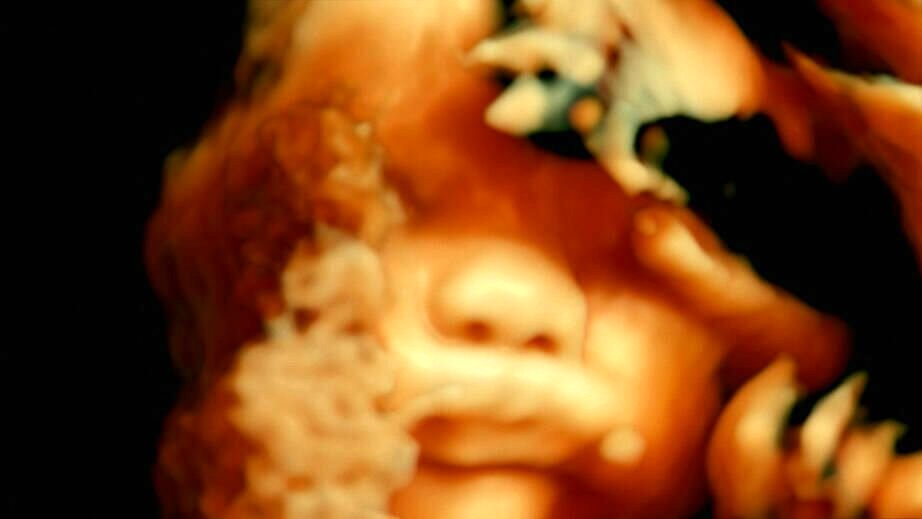

Five centuries ago, anatomist André Vésale opened up the human body to science for the first time in history. Today, De Humani Corporis Fabrica opens the human body to the cinema. It reveals that human flesh is an extraordinary landscape that exists only through the gaze and attention of others. As places of care, suffering and hope, hospitals are laboratories that connect every body in the world.